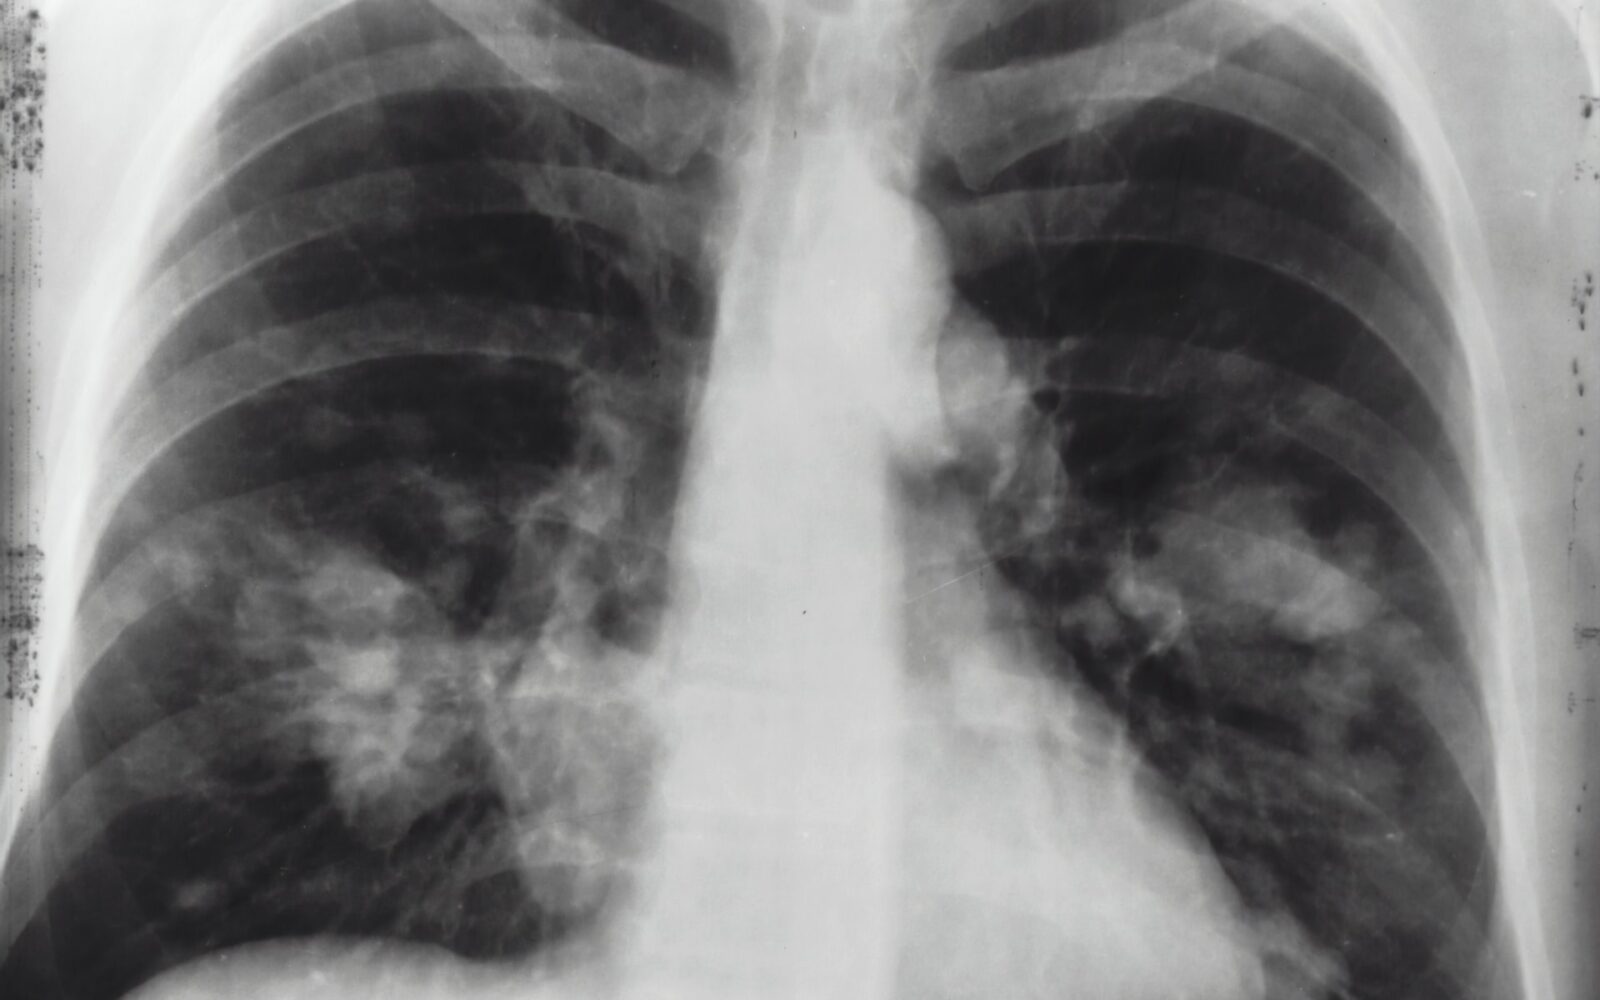

Dugi covid Dr. Jakopović: Post covid može izazvati fibrozu pluća što nekad završava transplantacijom - Kako je došlo ljeto i cijepljenje, imamo manje post covid bolesnika. Ima ljudi koji stvarno jako dugo zadržavaju teške plućne bolesti - nedostatak zraka pri najmanjem naporu, stalni kašalj. Najčešće to ide prema fibrozi pluća, st…